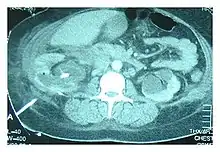

Abdominal ultrasonography and CT scan can help diagnose the underlying condition of the genitourinary tract. If other methods prove inconclusive, an accurate diagnosis can be made by a technetium 99m kidney scan, which shows albumin labeled 99Tc that translocates into the pleural space from the genitourinary tract.[4]